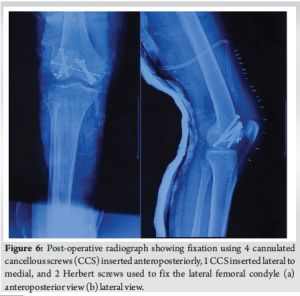

The fracture was approached through a standard medial parapatellar approach to gain access to both Hoffa fragments. The fracture site was exposed by everting the patella laterally and fully flexing the knee (Fig. 4). Anatomical reduction of the fracture fragments was obtained using 2 mm K-wires as joysticks for reduction in the distal fragments. Interfragmentary reduction clamps were deliberately avoided to prevent iatrogenic damage to the cartilage, considering the large degree of shear forces on the fracture fragments. Condylar reconstruction was done using 4 cannulated cancellous screws (7 mm), with 2 screws each passed anteroposteriorly to fix the lateral and medial femoral condyles. One additional screw was passed from lateral to medial to secure a metaphyseal beak fragment on the lateral side. The lateral Hoffa was found to have an additional fracture line, which warranted fixation with two additional headless Herbert screws (Fig. 5 and 6). The fixation construct was found to be stable throughout the knee range of motion (ROM). Post-operatively, static quadriceps strengthening alongside knee ROM exercises was started from the 3rd post-operative day with a hinged knee brace.